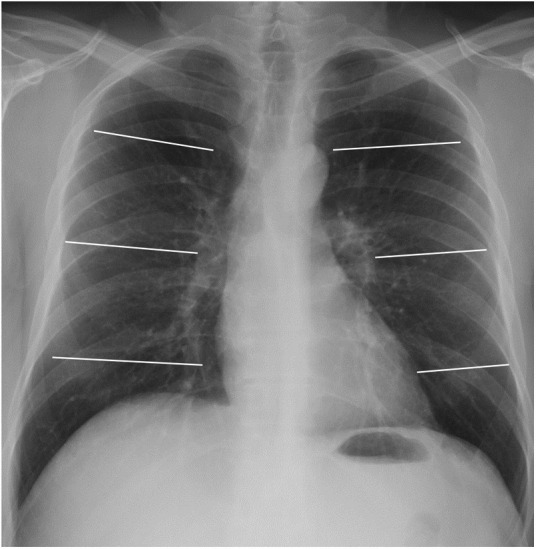

The first quantification system (6A) consisted of dividing each lung into three fields: upper, middle and lower (Fig. 1 ). According to this division, the extension of pulmonary opacities was classified as mild if only one field was affected, moderate if there were opacities in 2–3 lung fields, and severe if more than 3 fields were affected.

Figure 1.

Posteroanterior chest X-ray demonstrating division into 6 lung fields (quantification systems 6A and 6B) by two horizontal lines: upper lung field (from vertices to lower margin of the aortic knob), middle (lower margin of aortic knob to the middle third of heart border) and lower (middle third of heart border to costophrenic sinuses).

The second quantification system (6B) divided both lungs into the same six lung fields as 6A. In this case, mild extension corresponded to 1 or 2 affected lung fields, moderate extension to 3–4 fields and severe extension to 5 or more fields.

Finally, a third quantification system (8) divided both lungs into 8 lung fields, as reflected in Fig. 2 . The involvement of 1–3 fields implied a mild degree; this was deemed moderate when 4–6 fields were involved, and severe if 7 or 8 fields were affected.